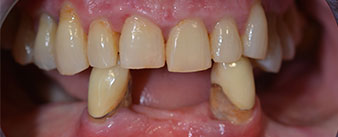

The 64-year-old patient presented with residual dentition of teeth 38, 33 and 43 and a clasp denture in the mandible (Fig. 1 and 2).